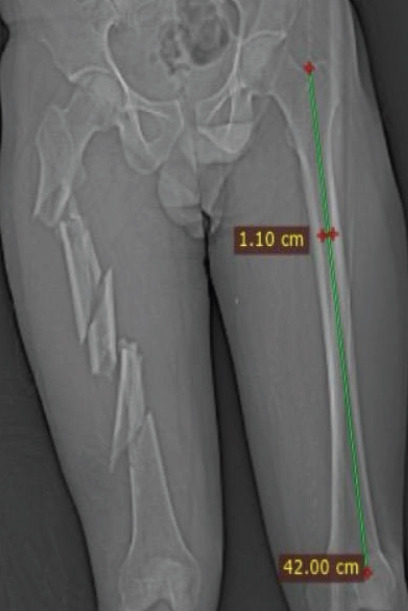

Case report: A 34-year-old male presented with multiple fractures, including a triple-segmental shaft femur fracture, following a high-energy road traffic accident. An intramedullary nail was used for closed reduction and internal fixation of the femur fracture, which provided stable fixation while preserving the blood supply and minimising soft-tissue damage.